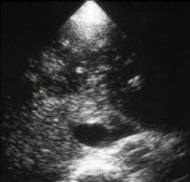

Гиперэхогенный центр

Гиперэхогенный центр 115 фотографий